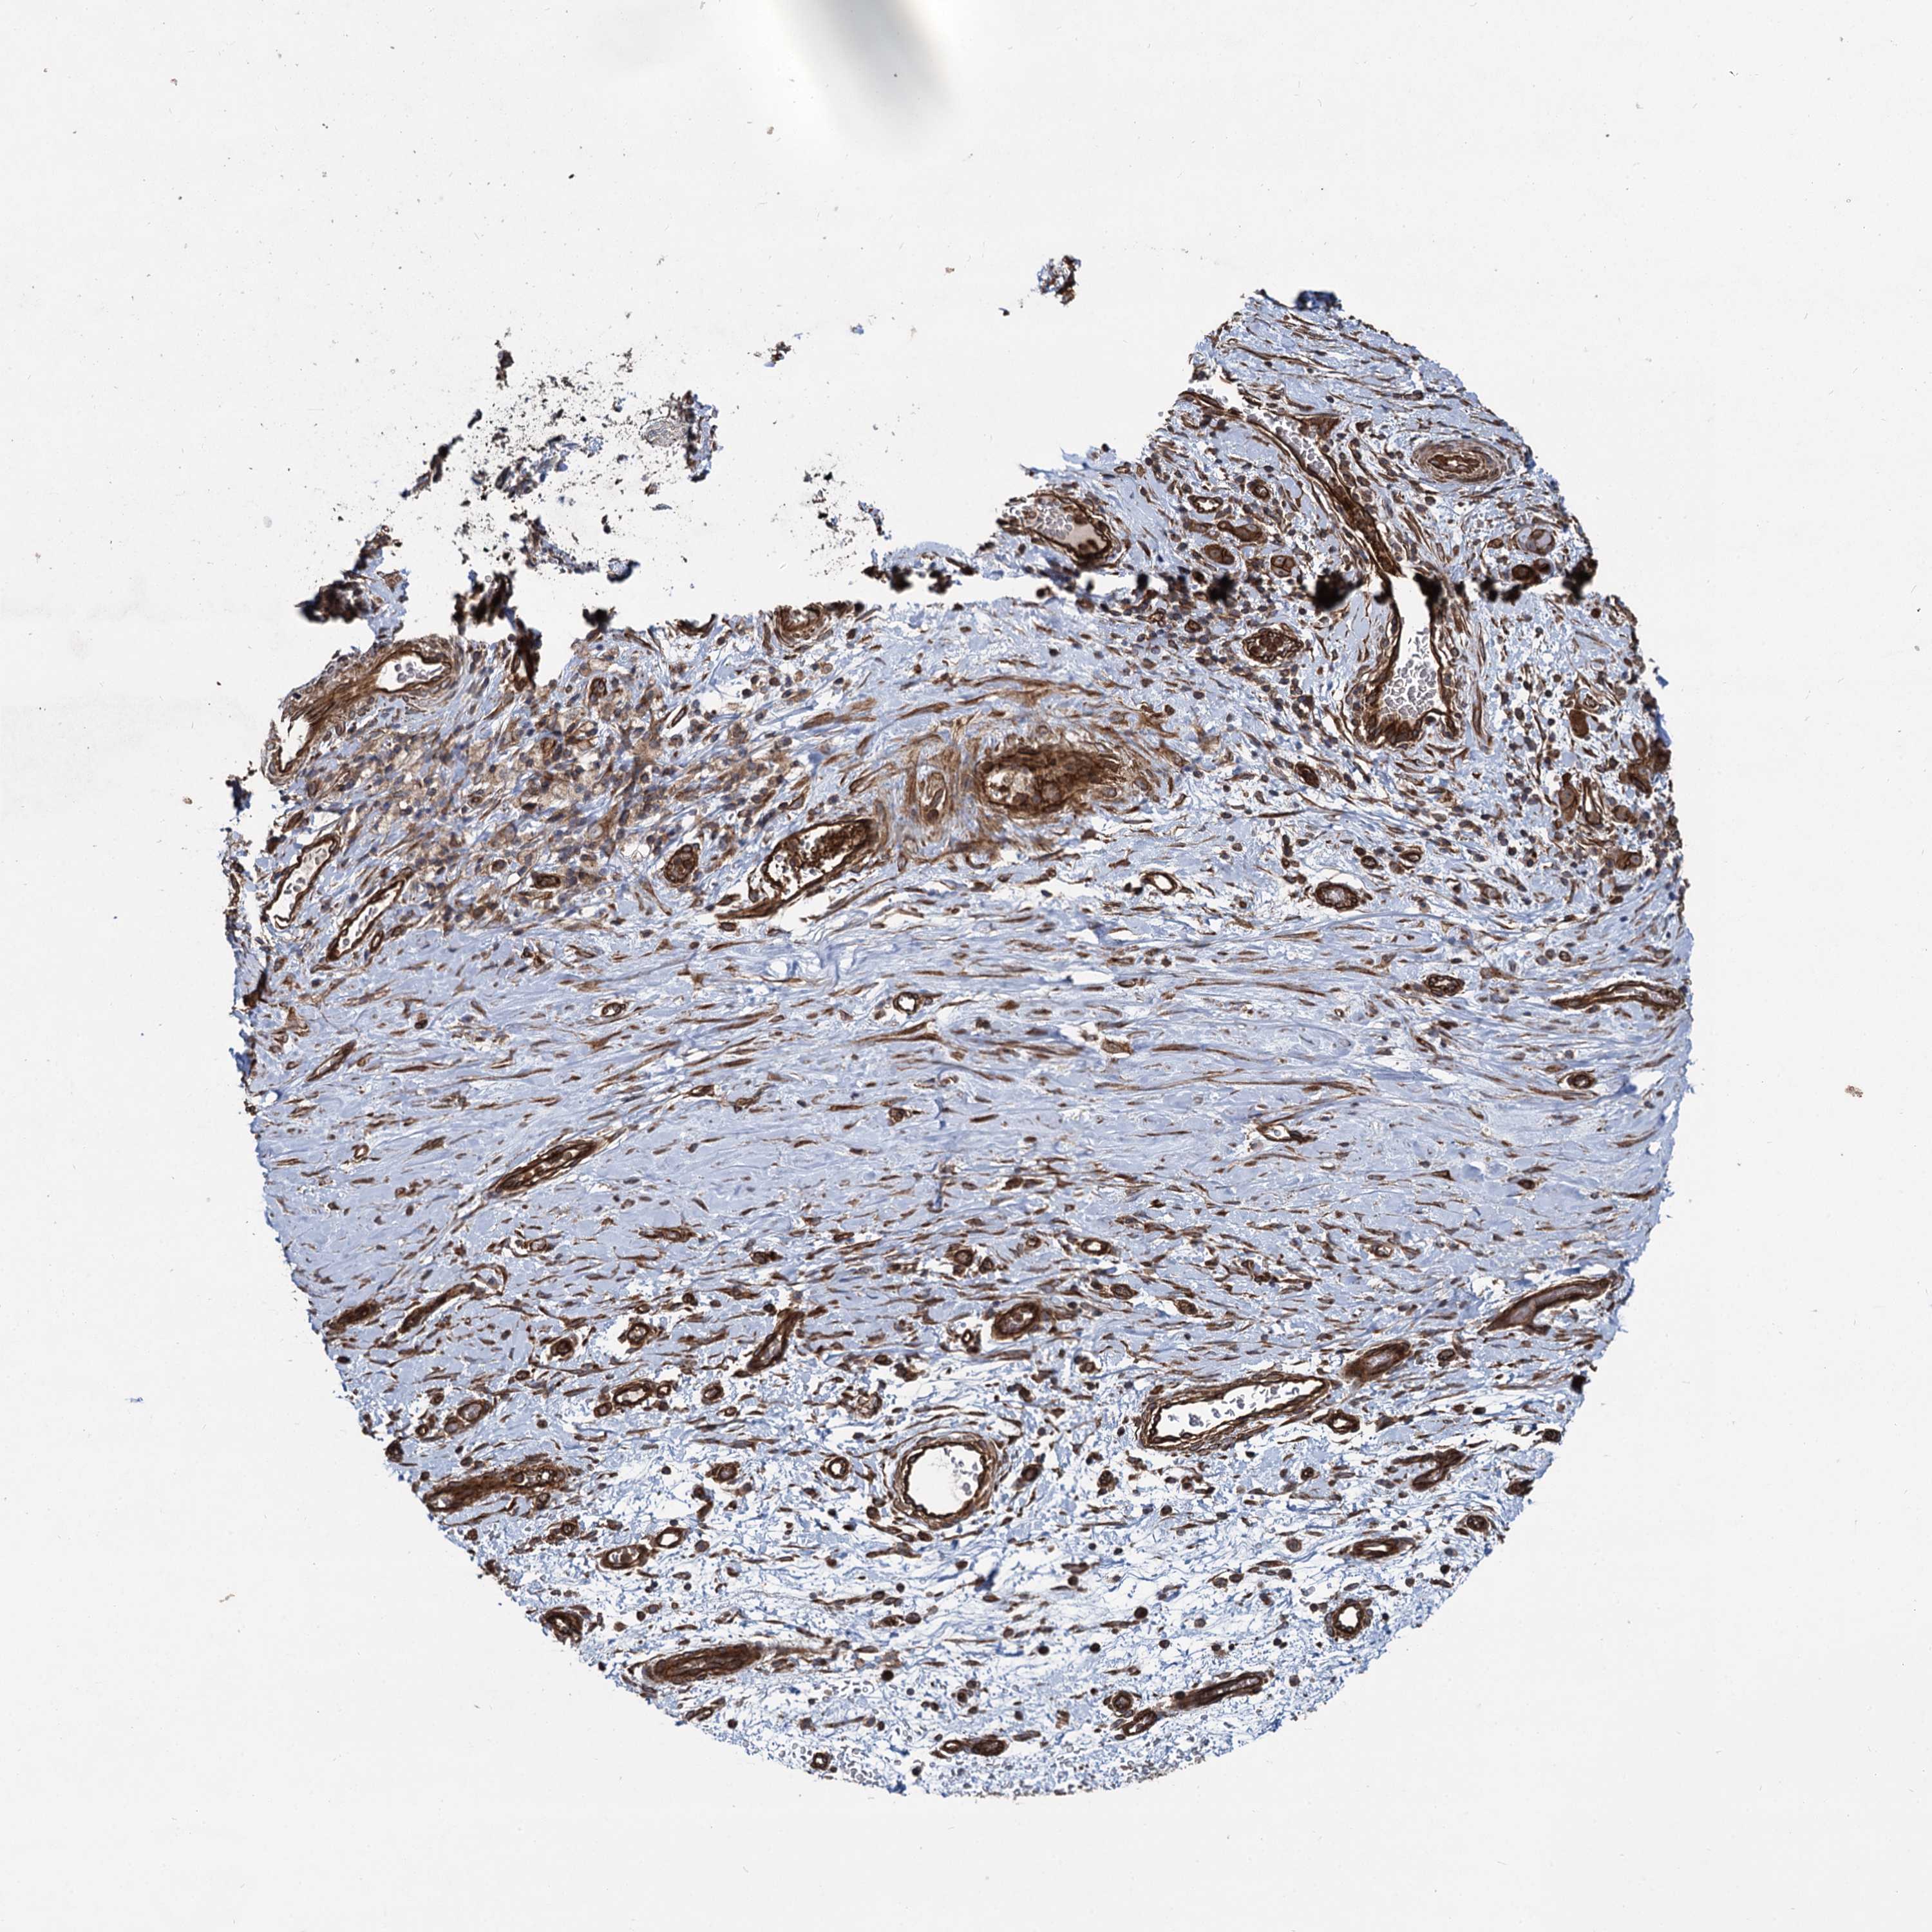

STOMACH CANCER - Protein expressioni

A mouse-over function shows sample information and annotation data. Click on an image to view it in a full screen mode. Samples can be filtered based on level of antibody staining by selecting one or several of the following categories: high, medium, low and not detected. The assay and annotation is described here.

Note that samples used for immunohistochemistry by the Human Protein Atlas do not correspond to samples in the TCGA dataset.

Antibody stainingi

Antibody staining in the annotated cell types in the current human tissue is reported as not detected, low, medium, or high, based on conventional immunohistochemistry profiling in selected tissues. This score is based on the combination of the staining intensity and fraction of stained cells.

Each image is clickable and will lead to virtual microscopy that enables deeper exploration of all samples and also displays staining intensity scores, fraction scores and subcellular localization as well as patient and tissue information for each sample.

Antibody HPA039807

Staining

High

Medium

Low

Not detected

Intensity

Strong

Moderate

Weak

Negative

Quantity

>75%

75%-25%

<25%

None

Location

Nuclear

Cytoplasmic/membranous

Cytoplasmic/membranous,nuclear

Adenocarcinoma, NOS

Adenocarcinoma, High grade